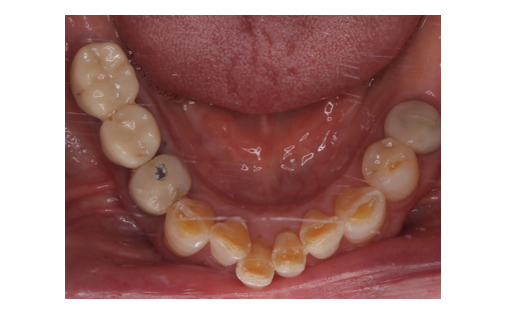

歯の移植の症例

Before

After

歯の移植をしたレントゲン写真です。